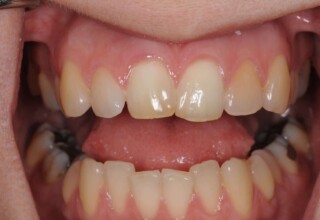

Restoration of bilateral diastemas between central and lateral incisors.

Diastemas were created mainly because of narrow laterals. After orthodontic treatment was finalized, the diastemas were closed with two composite resin restorations.